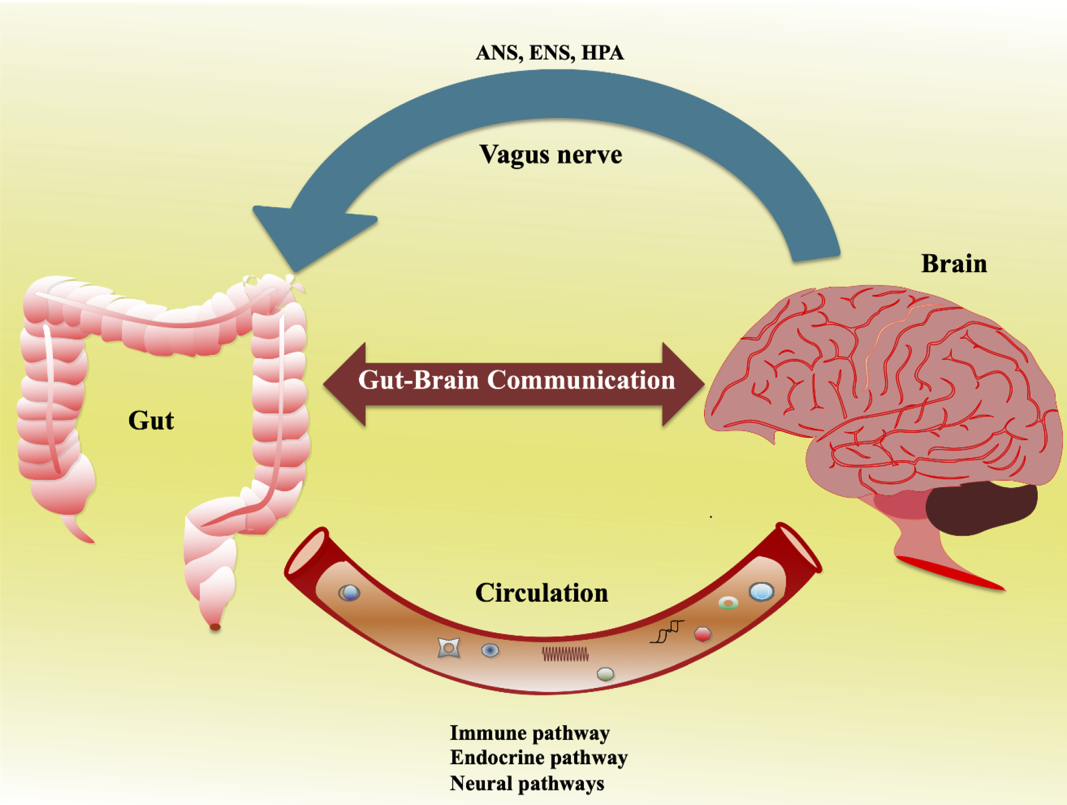

The gut-brain axis forms a bustling superhighway of communication between your digestive tract and your brain, and new research is revealing just how vital this connection is. In 2024, a report in *Nature Reviews Neuroscience* highlighted that your gut is home to around 100 trillion microorganisms, which send signals to your brain through the vagus nerve and via chemical messengers. About 90% of the body’s serotonin—a neurotransmitter that stabilizes mood—is actually produced in the gut, not the brain. These gut microbes can also influence dopamine and gamma-aminobutyric acid (GABA) levels, which are both essential for mood regulation and cognitive function. The gut-brain axis has become a core focus for neuroscientists, as disruptions here are now strongly associated with anxiety, depression, and even cognitive decline. Researchers are especially interested in how gut health interventions may help prevent or treat mood disorders. In 2025, scientists are taking this connection more seriously than ever, with several clinical trials underway to test how improving gut health might relieve symptoms of depression and anxiety.

Chronic inflammation is a silent saboteur when it comes to mental well-being. *Psychological Medicine* (2025) reported that individuals with major depressive disorder often have elevated levels of inflammatory markers, such as C-reactive protein (CRP). The gut microbiome strongly influences inflammation: specific beneficial bacteria produce short-chain fatty acids (SCFAs) like butyrate, which help dampen inflammatory responses throughout the body. If the gut barrier becomes “leaky” due to poor diet or stress, harmful bacteria and toxins can enter the bloodstream, triggering systemic inflammation that can reach the brain. This inflammatory cascade is now recognized as a contributor to anxiety, depression, and brain fog. New therapies are being explored to rebalance gut bacteria as a means of reducing brain inflammation and improving mood stability.

Stress doesn’t just affect your mind; it can quickly disrupt your gut, too. A 2024 study in *Frontiers in Psychology* tracked over 1,200 adults and found that those experiencing chronic stress had a 40% reduction in beneficial gut bacteria like Lactobacillus and Bifidobacterium. Stress hormones such as cortisol alter the gut environment, leading to dysbiosis—a harmful imbalance of gut microbes. This, in turn, can increase gut permeability and inflammation, worsening anxiety and depressive symptoms. Techniques like mindfulness meditation, deep breathing, and yoga were found to help restore gut balance by lowering stress-induced inflammation. The bidirectional nature of the gut-brain axis means that reducing stress can directly support gut health, and vice versa.

Gut bacteria are surprisingly powerful when it comes to producing and regulating neurotransmitters. The *Nature Communications* study from 2024 revealed that certain strains of gut bacteria can synthesize GABA, which helps calm the nervous system and reduce anxiety. Other microbes are involved in the production of dopamine and serotonin, both vital for feelings of well-being and motivation. The gut also influences levels of brain-derived neurotrophic factor (BDNF), which supports learning, memory, and neuroplasticity. Disruptions in these gut-driven processes can lead to mood swings, irritability, and even cognitive decline. Researchers are now focusing on how targeted changes to the gut microbiome could offer new hope for treating mood disorders.